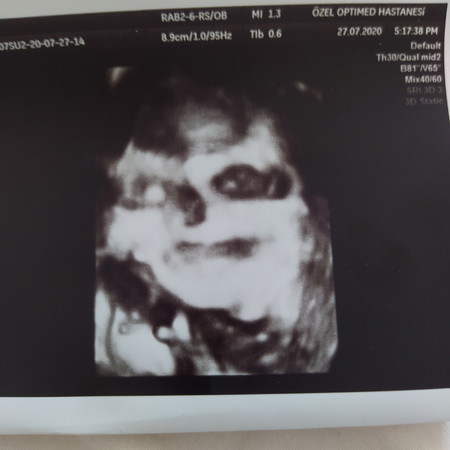

ตั้งครรภ์34วีค ไปอัลตร้าซาวด์มาค่ะ รูปลูกแบบนี้คือลืมตา อ้าปากใช่ไหมคะ (แอบกลัวลูกตัวเอง 555:))